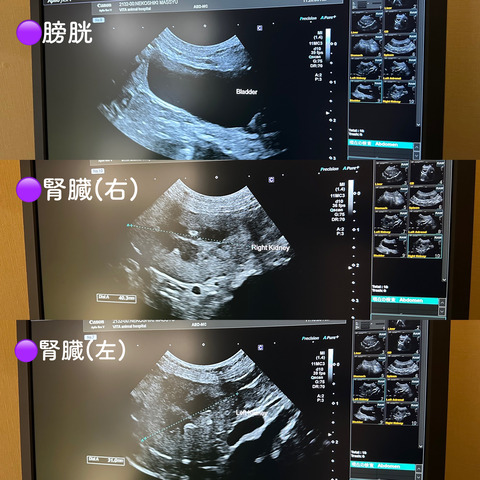

レントゲンや超音波検査もやりました

▼超音波

先生いわく、特に異常はないそうです